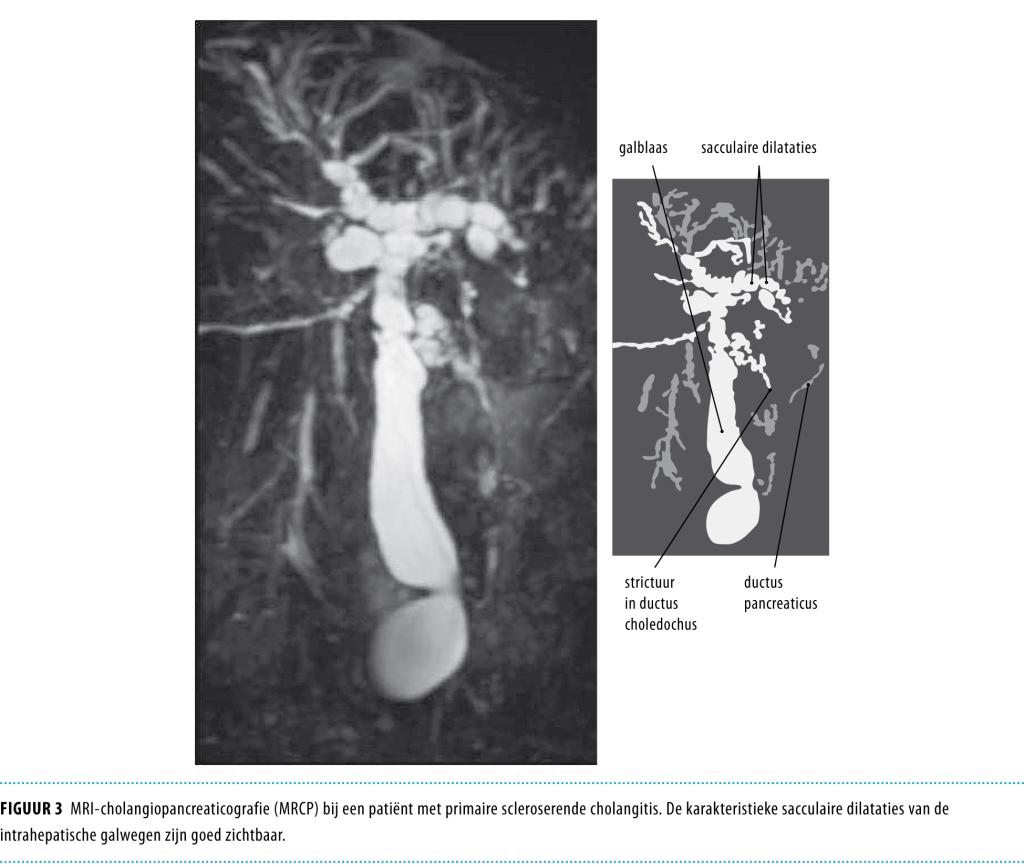

• De diagnose wordt gesteld op basis van leverenzymwaarden die wijzen op cholestase en karakteristieke galwegafwijkingen bij cholangiografie of in het leverbiopt, na het uitsluiten van andere oorzaken.